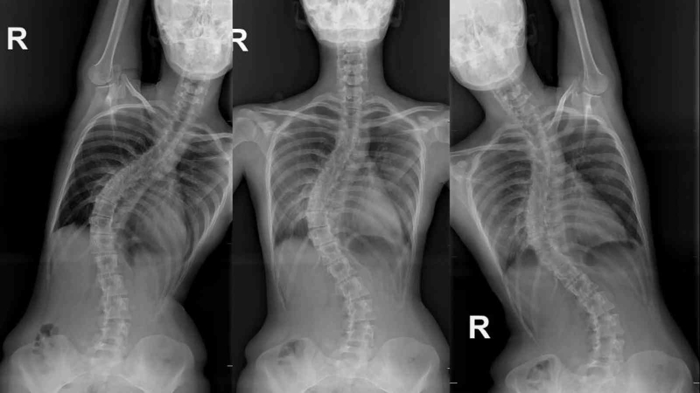

Aleksandra'nın kendilerine skolyoz şikâyetiyle geldiğini belirten Opr. Dr. Yunus Uysal, "Rusya'dan bize filmlerini gönderdiğinde omurgasında yaklaşık 60 derecelik bir eğriliği vardı. Ameliyat olması gerektiğini ilettik. Bizim önerimiz doğrultusundan Rusya'dan Türkiye'ye geldi. Burayı tercih etmesinin sebebi, Türkiye'deki tıp uygulamalarının üst seviyede olması olmuş. Kurumumuzda mevcut olan robotik omurga cerrahisini tekniğinden faydalanarak skolyoz ameliyatını gerçekleştirdik. Ameliyattan önce 60 derece olan eğriliği, neredeyse '0' derecesine kadar düzelttik ve yüz güldürücü bir sonuç aldık" diye konuştu.